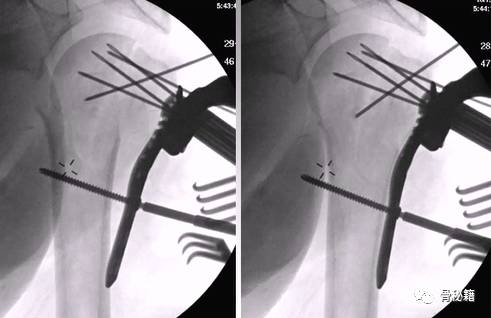

腋位的翘拨复位

解剖钢板与提拉螺钉的复位

需要注意 不要应用过度提拉 使得内侧肱骨距过复位

注意完成内侧支撑和内外翻的复位

在此病例中,为了复位良好,舍弃了肱骨近端与钢板贴服